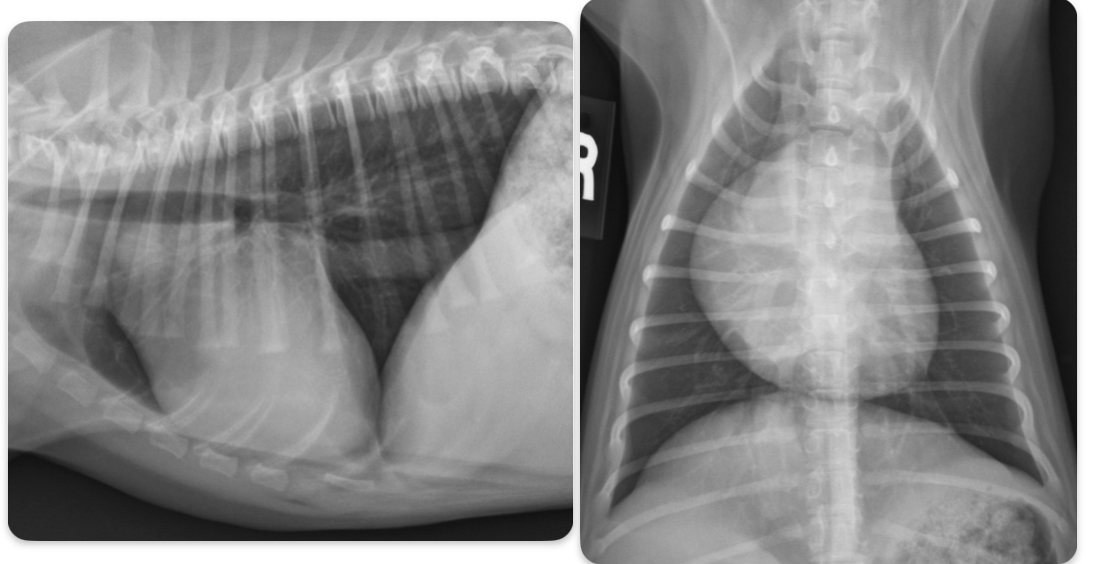

What is going on with this cat heart?

Microcardia